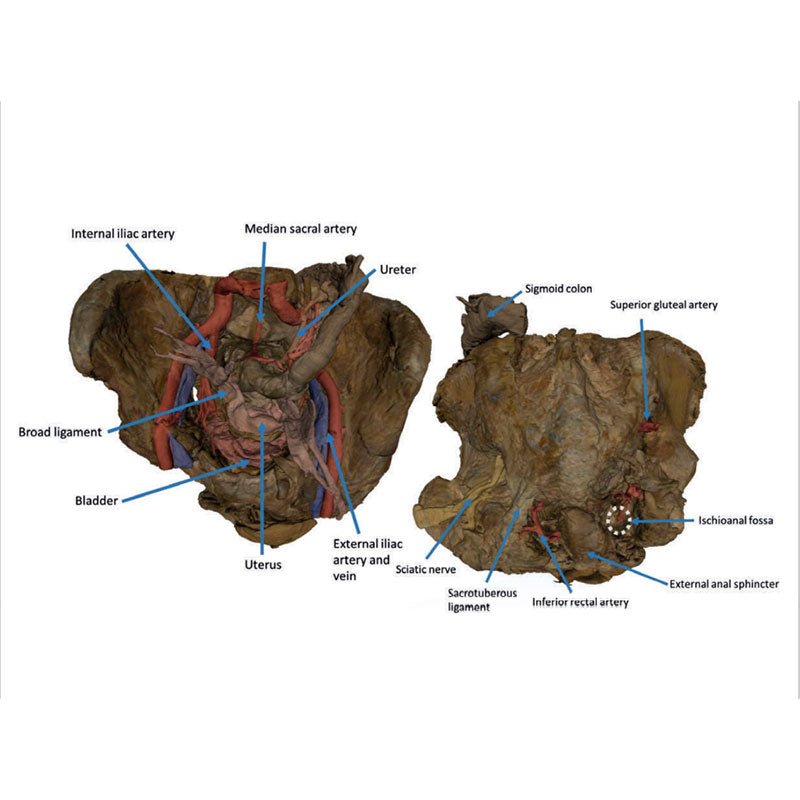

This 3D model presents a deep dissection and isolation of the pelvis from surrounding regions, particularly

demonstrating visceral and neurovascular structures relative to deep ligaments and osseous features.

Within the false pelvis, the sigmoid colon descends on the left side of the specimen to the rectum, passing

superficially across the pelvic brim and the passage of the common and external iliac artery and vein. Adjacent

to the sigmoid colon are parts of the sigmoid arteries and superior rectal artery, resting superficial to the

common iliac vessels and near the descending ureter. Anterior in the true pelvis is the collapsed urinary

bladder, and between the bladder and rectum rests the uterus. The organ is partially covered in the broad

ligament, with both the suspensory ligament of the ovary and round ligament have been separated and pulled away

from the peritoneum on both sides to expose surrounding blood vessels. While the ovarian ligaments, round

ligaments, uterine tubes and ovaries are trapped within the peritoneal fold of the broad ligament, the reduction

in ovary size (common with advanced age) has rendered these indistinguishable in the model.

Lateral to these organs, branches of the internal iliac artery can be identified – as well as a retained median

sacral artery in the midline between the two common iliac arteries. On the left side only the uterine artery can

be seen laterally. On the right side, the obturator, superior vesical, and uterine arteries can be observed. In

addition, the origins of the inferior epigastric artery and vein can be seen arising from the external iliac

vessels just prior to exiting the inferior abdominal cavity.

On the right side of the preserved pelvis, the entire femur and thigh musculature has been removed to

demonstrate the obturator membrane, the articular cartilage of the acetabulum and the transverse ligament of the

acetabulum. Posteriorly the entire gluteal region has been dissected to expose the superior gluteal foramen and

the origin of the superior gluteal artery. The sacrotuberous ligament has been removed to demonstrate the

sacrospinous ligament, with some branches of the inferior rectal artery retained within the exposed ischoanal

fossa.

On the left side of the preserved pelvis the sciatic nerve has been maintained within the greater sciatic

foramen, as has the sacrotuberous ligament. The ischioanal fossa mirrors that of the right side, where branches

of the inferior rectal artery have been retained relative to the fibres of the pelvic diaphragm, and the

integration of the external anal sphincter on the projecting external rectal surface.